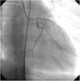

Familial hypercholesterolemia (FH) is a genetic disorder characterized by high cholesterol levels, specifically very high levels of low-density lipoprotein (LDL, "bad cholesterol"), in the blood and early cardiovascular disease.The most common mutations diminish the number of functional LDL receptors in the liver. Since the underlying body biochemistry is slightly different in individuals with FH, their high cholesterol levels are less responsive to the kinds of cholesterol control methods which are usually more effective in people without FH (such as dietary modification and statin tablets). [Source: Wikipedia ]